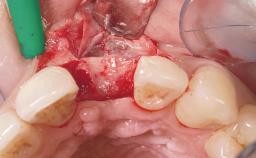

Bone Augmentation Horizontal|Simultaneous

Augmentation Materials Autogenous chips|Xenogenous|Membrane

Bone Volume Deficient horizontally, allowing simultaneous augumentation